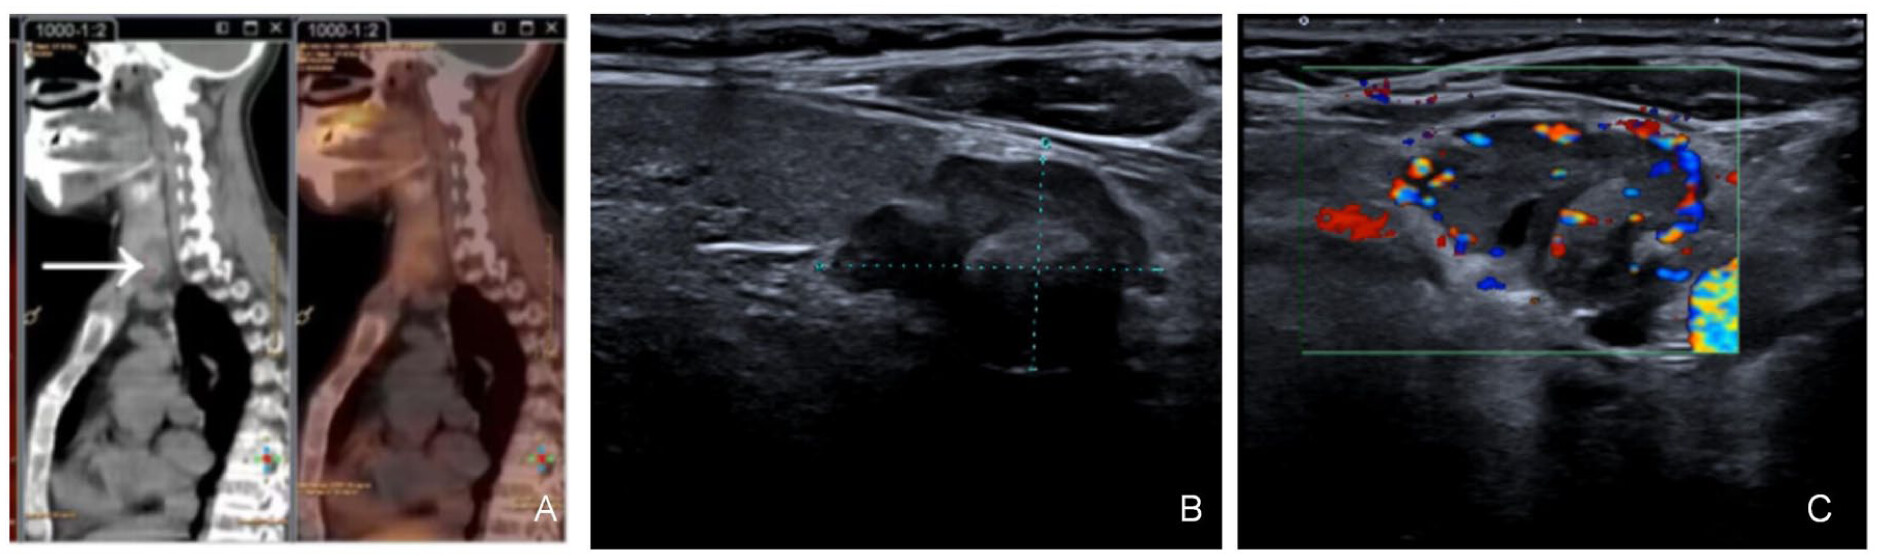

The patient is a 44-year-old woman who presented with a 2-month history of intermittent chest pain without obvious triggers. The pain progressively worsened, predominantly localized to bilateral costal arches, exacerbated by physical activity, and nonradiating. Associated symptoms included fatigue, bradykinesia (slowness of movement), and intermittent claudication during ambulation. Bone density lumbar spine examination suggested osteoporosis. She was admitted to the Department of Endocrinology of our hospital with parathyroid hormone (PTH) examination of 1782 pg/mL (reference range: 15–65 pg/mL) and blood calcium of 3.54 mmol/L (reference range: 2.2–2.65 mmol/L). The diagnosis was hypercalcemia, hyperparathyroidism, and osteoporosis. She had a positive salmon calcitonin test sensitivity and was given symptomatic treatment with fluid replacement, hypocalcemic therapy (Ibandronate sodium monohydrate, Elcatonin), and diuresis. Despite 48 h of treatment, serum calcium levels rose to 3.9 mmol/L, prompting initiation of continuous renal replacement therapy (CRRT). Post-CRRT, calcium levels normalized to 2.475 mmol/L, with resolution of chest pain, CRRT was discontinued, and maintenance therapy with fluids, calcium-lowering agents, and diuretics resumed. However, calcium levels rebounded to 2.93 mmol/L within 48 h. Ultrasonography of the parathyroid glands showed that an uneven hypoechoic structure, measuring about 2.28 × 1.56 cm (Figure 1(b) and (c)), with fuzzy edges and irregular borders, was seen in the lower pole of the left lobe of the thyroid gland, and was characterized by abundant blood flow signals. Dual time-phase parathyroid examination showed that there were nodular shadows with slightly increased radioactivity distribution in the middle and lower part of the right lobe of the thyroid gland and in the lower part of the left lobe of the thyroid gland, which was considered to be the possibility of hyperfunctioning parathyroid tissue; and there was unevenly decreased bone density in the neck, bones of the thorax, and the upper part of the humerus bilaterally, with bone damage visible, which was considered to be the possibility of a brown tumor. Consultation with the Department of Thyroid Surgery was requested, Thyroid surgery consultation recommended parathyroidectomy.

Figure 1. Imaging of parathyroid cancer. (a) Parathyroid bisphosphate examination. (b) Hypoechoic left lobe of the thyroid gland below the lower pole, approximately 2.28 × 1.56 cm in size. (c) The blood flow signal within it is abundant.